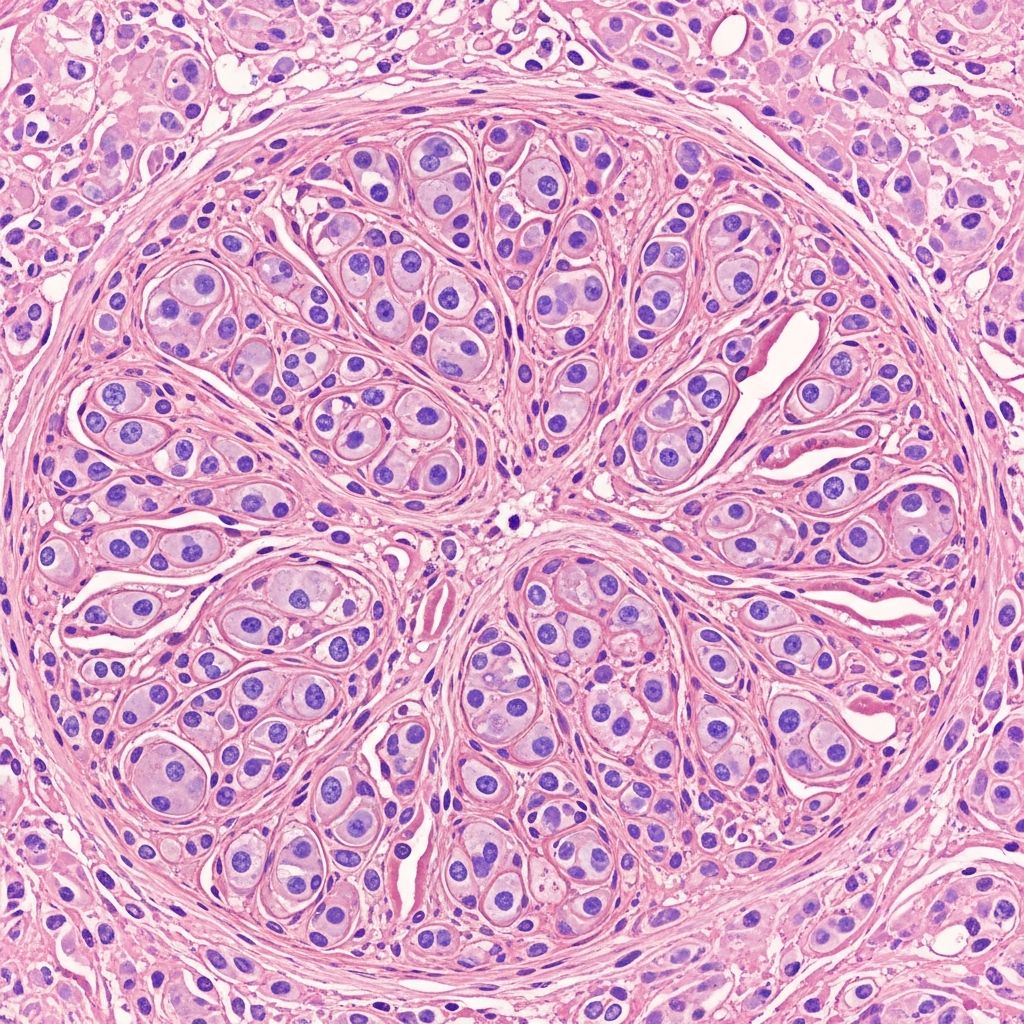

At low magnification, pilar sheath acanthoma displays a lobular proliferation of benign squamous epithelium within the dermis, centred around small cystic spaces that connect to the epidermal surface via a dilated pore filled with keratinous debris (figures 1 and 2). These epithelial lobules radiate outward from the central cystic cavity, extending into the deep dermis or even subcutis, composed of bland keratinocytes without atypia or mitoses.

The lining of the cystic spaces varies: some exhibit a prominent granular layer akin to epidermoid cysts (figure 3), while others show an attenuated granular layer resembling trichilemmal cysts (figure 4). Clear cells with glycogen-rich cytoplasm are frequently observed within the lobules (figures 5 and 6), indicative of outer root sheath differentiation. An eosinophilic basement membrane often surrounds the lobules, further supporting follicular sheath origin. No fibrovascular stroma or hair shaft formation is present, distinguishing it from other adnexal tumours.